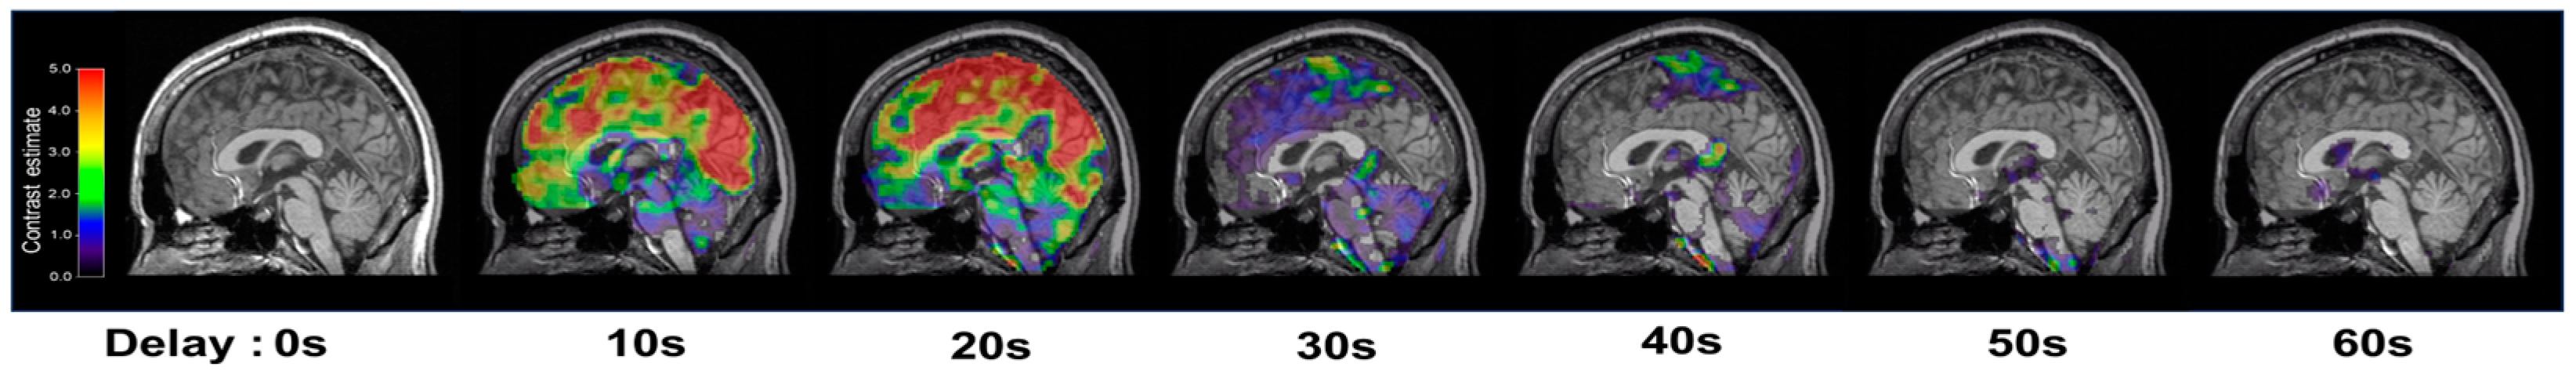

To account for the temporal lag between 5% CO2 inhalation and its subsequent cerebrovascular effects, which are known to occur within tens of seconds in the GM [2,20], we performed a stimulus timing corrected analysis using the SPM12 first-level analysis function. This involved evaluating potential timing corrections in increments of one TR (2.5 s). Given that cerebrovascular responses to hypercapnic stimuli are subject to physiological delays—primarily due to the gas delivery system and respiratory dynamics—they typically emerge within approximately 10 to 30 s after stimulus initiation [2,20]. To accurately align the modeled CO2 onset with the observed BOLD signal change, we sought to identify the optimal physiological delay.

To this end, we systematically shifted the modeled onset of the CO2 stimulus in each participant’s first-level general linear model (GLM), applying delays in 2.5 s increments (the fMRI sampling rate, TR) across a 0 to 50 s range. For each shifted onset, beta-maps were computed for all participants. Subsequently, a one-sample t-test was performed at each time point across subjects to evaluate the group-level response. The physiological delay was determined by identifying the time point at which the mean beta values across the whole brain reached their maximum. This peak was observed at 20 s, which was then applied as the optimized delay in modeling the CO2 stimulus onset (Figure 3). This timing correction was then applied to the transition from air to CO2 inhalation periods. Consequently, the mean BOLD signals for the air inhalation periods were extracted from 0 to 120 s and 261 to 380 s, while the mean BOLD signals for the CO2 inhalation periods were extracted from 141 to 260 s and 381 to 500 s, effectively incorporating the 20 s stimulus timing correction. Finally, the stimulus timing corrected MRI (tcMRI) CVR was calculated as in (1):

Figure 3.

Representative brain sagittal images with the levels of activation during inhalation of 5% CO2, which was identified by statistical parametric mapping (SPM) first level analysis.